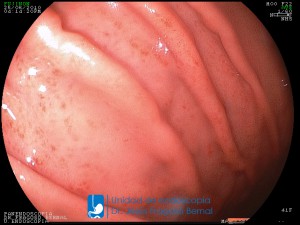

La Unidad de Endoscopía fue creada en 2002 por el Dr. Jesús Fragoso Bernal, es pionera en el estado por la utilización de la tecnología más avanzada, que nos permite ofrecer servicios integrales de diagnóstico y tratamiento para las enfermedades del aparato digestivo.

El profesionalismo de nuestro personal, altamente especializado, se distingue por la calidad y calidez de nuestros servicios con el objetivo de brindar una atención de excelencia en el ambiente más confortable para comodidad y seguridad de nuestros pacientes.

"La Unidad de Endoscopía se ha caracterizado por un progreso continuo desde su inicio marcando la pauta en los procedimientos endoscópicos en el estado de Tlaxcala y estando siempre a la vanguardia tecnológica."

Dr. Jesús Fragoso Bernal